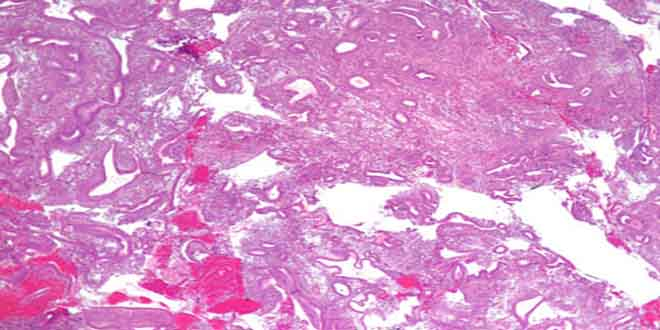

Tăng sinh nội mạc TC là chẩn đoán mô học được định nghĩa là có sự tăng sinh bất thường về kích thước và hình dạng của tuyến NMTC làm tăng tỷ lệ tuyến / mô đệm so với nội mạc TC bình thường.

- Thành phần cấu trúc tuyến/mô đệm (đơn giản hay phức tạp).

- Có sự hiện diện của nhân không điển hình (điển hình hay không điển hình).

Do đó tăng sinh NMTC được chia thành 4 nhóm

- Tăng sinh đơn giản điển hình.

- Tăng sinh đơn giản không điển hình.

- Tăng sinh phức tạp điển hình.

- Tăng sinh phức tạp không điển hình.

Tăng sinh NMTC là chẩn đoán của GPB trên vi thể nên nạo sinh thiết giúp chẩn đoán rõ ràng dạng tăng sinh.